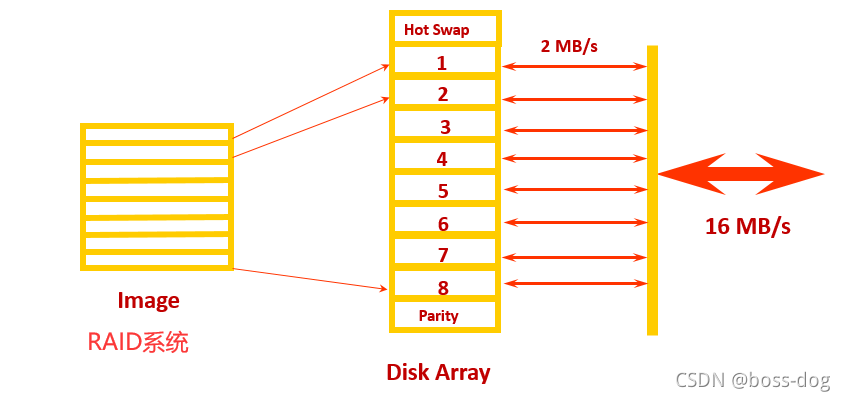

图像数据库(RAID)的作用:

1.支持在线(快速存取)图像、文件的存储和分发装置(比如做急诊的话,需要将CT图像尽快交给医生去做判断)

2.支持同步图片、文件的输入和输出转移操作

3.最多可以保存三个月的图片、文件,超过三个月的可以通过光盘等存储

4.拥有可衡量的数据处理能力